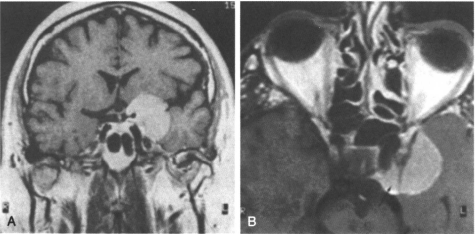

蝶骨嵴脑膜瘤约占幕上脑膜瘤的20%,其中不到一半起源于蝶骨嵴内侧。在各种病例组中,中年女性均有好发倾向。症状的出现具有隐蔽性,通常要经过2年时间才就医。在我们的20例病例组中和其他的病例组中,视力下降是较常见的主诉。视野异常是多种多样的,依赖于视交叉和视朿受累情况而定。视乳头检査通常显示视神经萎缩,和较少见的对侧视乳头水肿( Foster-kennedy综合征)。当肿瘤累及海绵窦和眶上裂时,出现眼球运动障碍和面部感觉减退。突眼是因为肿瘤延仲至眼眶内和海绵窦所致。头痛和眶区疼痛可能在视力症状出现之前数年即出现。经常见到智能减退和认知改变,待别是在肿瘤位于优势半球的老年患者。轻偏瘫、失语和癲痫不常见。

据报道蝶骨嵴内侧脑膜瘤外科治疗组有很高的病残率和死亡率。在 Cushing较初的13例病例组中,有2例在围手术期内死亡,只有3例有全切的可能,多数存活病人有的神经功能障碍,其中5例最终死于肿瘤复发。 Cushing和 Eisenhardt记录切除肿瘤较困难的地方在于分离颈内动脉分叉处与血管相缠绕的肿瘤。他们提醒手术医生进入颈内动脉区域的风险。在其后全部的手术病例组屮,前循环主要血管的损伤是手术死亡和病残的主要原因,即使是在有手术显微镜和常规使用手术显微镜后也是如此。1953年 Uihlein和 Weyand报告的52例中,手术死亡率为33%。1970年 Konovalov和同伴一组70例病人组中,手术死亡率为19%,手术全部是用手术显微镜来进行的。蝶骨嵴内侧脑膜瘤手术病残包括偏瘫、下丘脑梗死、失语、植物神经功能紊乱、视力下降和复视。在个研究中,23%的存活者有严重的病残。更近期的报告显示了手术死亡率、病残率及治愈率的好转。在颅内脑膜瘤中,蝶骨嵴内侧脑膜瘤是复发率较高的脑膜瘤之一。复发与初始手术留下的残留肿瘤相关。在 Mirirmano和同伴所作的研究中,蝶骨嵴内侧脑膜瘤的5年、10年复发或进展率分别为34%和54%,与之相比,凸面脑膜瘤的5年、10年复发率分别是3%和25%。